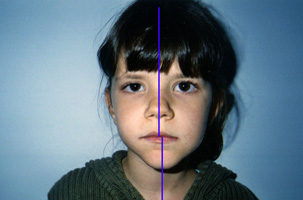

Γνάθοι που είναι δυσανάλογες με το υπόλοιπο πρόσωπο ως προς το μέγεθος ή/και τη θέση.